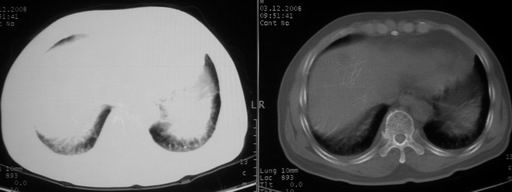

男,78岁,咳嗽、咳痰、发热入院,抗炎治疗一周后已退热,咳血似痰。

10月9日片:

ct左肺下叶大片状高密度影,病变密度不均,界限不清,左侧胸腔积液,治疗后复查临床症状好转而影像学表现病变有发展,还是首先考虑感染性病变,复查时间短附合感染性病变的病理改变。

两肺炎症感染(以左肺下叶为著),双侧少量胸腔积液;建议继续抗炎治疗。